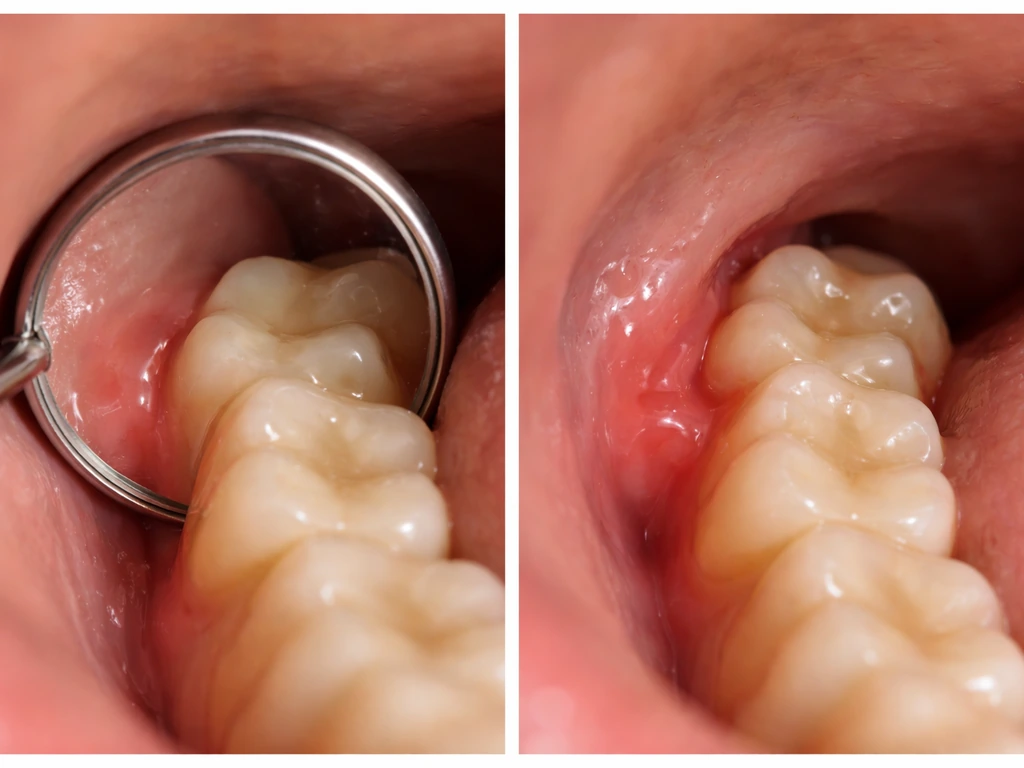

It is also worth clearing up a myth right here: your gums and the surrounding tissue are not going to regenerate their way around the problem. Some people assume the tissue will simply adapt or '<a data-article-id="A5CB5C36-86EF-4738-8F0A-62B090B0D560">grow back</a>' to accommodate the tooth naturally, but the biology does not work that way. The gum may cover a partially erupted tooth, creating a flap called a pericoronal flap, but that flap does not resorb or helpfully reshape on its own. It stays, traps food and bacteria underneath it, and becomes a recurring inflammation source unless the situation is actively managed. If you have been reading about dental regeneration elsewhere on this site, this is one of those cases where waiting for the body to fix itself is not a realistic plan.

- Pericoronitis: infection under the gum flap covering a partially erupted tooth. Signs include throbbing pain, visibly swollen and red gum tissue, pus or a bad taste, fever, and difficulty opening your mouth (trismus). The trigeminal nerve pathways mean this can cause severe head and neck pain that feels out of proportion to what you can see in the mirror.

Wisdom tooth eruption does not happen overnight. The tooth moves in stages over months or even years, and pain flares tend to follow that pattern. Many people have their first notable discomfort when the tooth is just starting to poke through the gum surface, a phase where the gum is partially open but the tooth is not fully through. That partial opening is the most trouble-prone period because it creates a small pocket that traps food and bacteria.

| Swollen, red gum flap with bad taste | After partial eruption with food trapping | Pericoronitis, needs dentist evaluation |

Deep cleaning around the erupting tooth

If pericoronitis is the issue but the infection has not spread, a thorough professional cleaning to irrigate and debride the area under the gum flap is often the first step. Your dentist may use a dental pick, syringe irrigation, or an ultrasonic scaler to flush out food debris and bacterial buildup. This alone often brings significant relief within 24 to 48 hours.